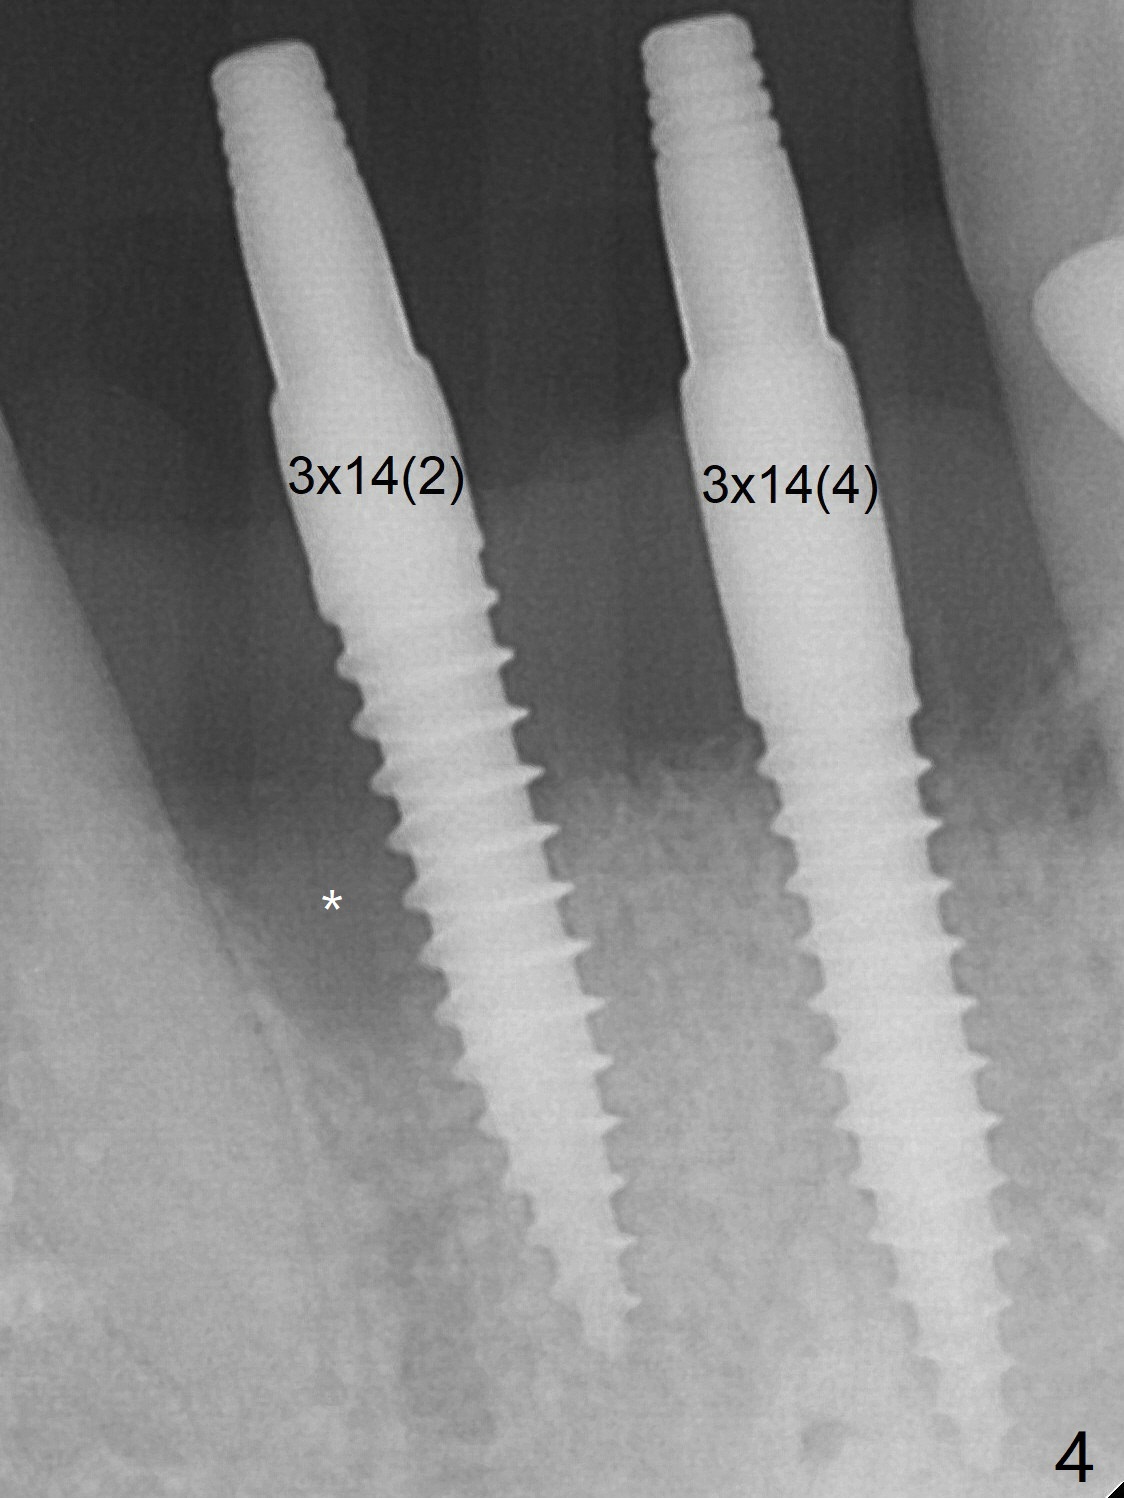

When dummy implants are placed partially, there is a large bony defect (Fig.4 *). After final implants (3x14(4) mm) are placed, allograft is placed coronally (Fig.5 *). Hard tissue heals 5.5 months postop (Fig.10 with formation of apparent bony trabeculae: *).